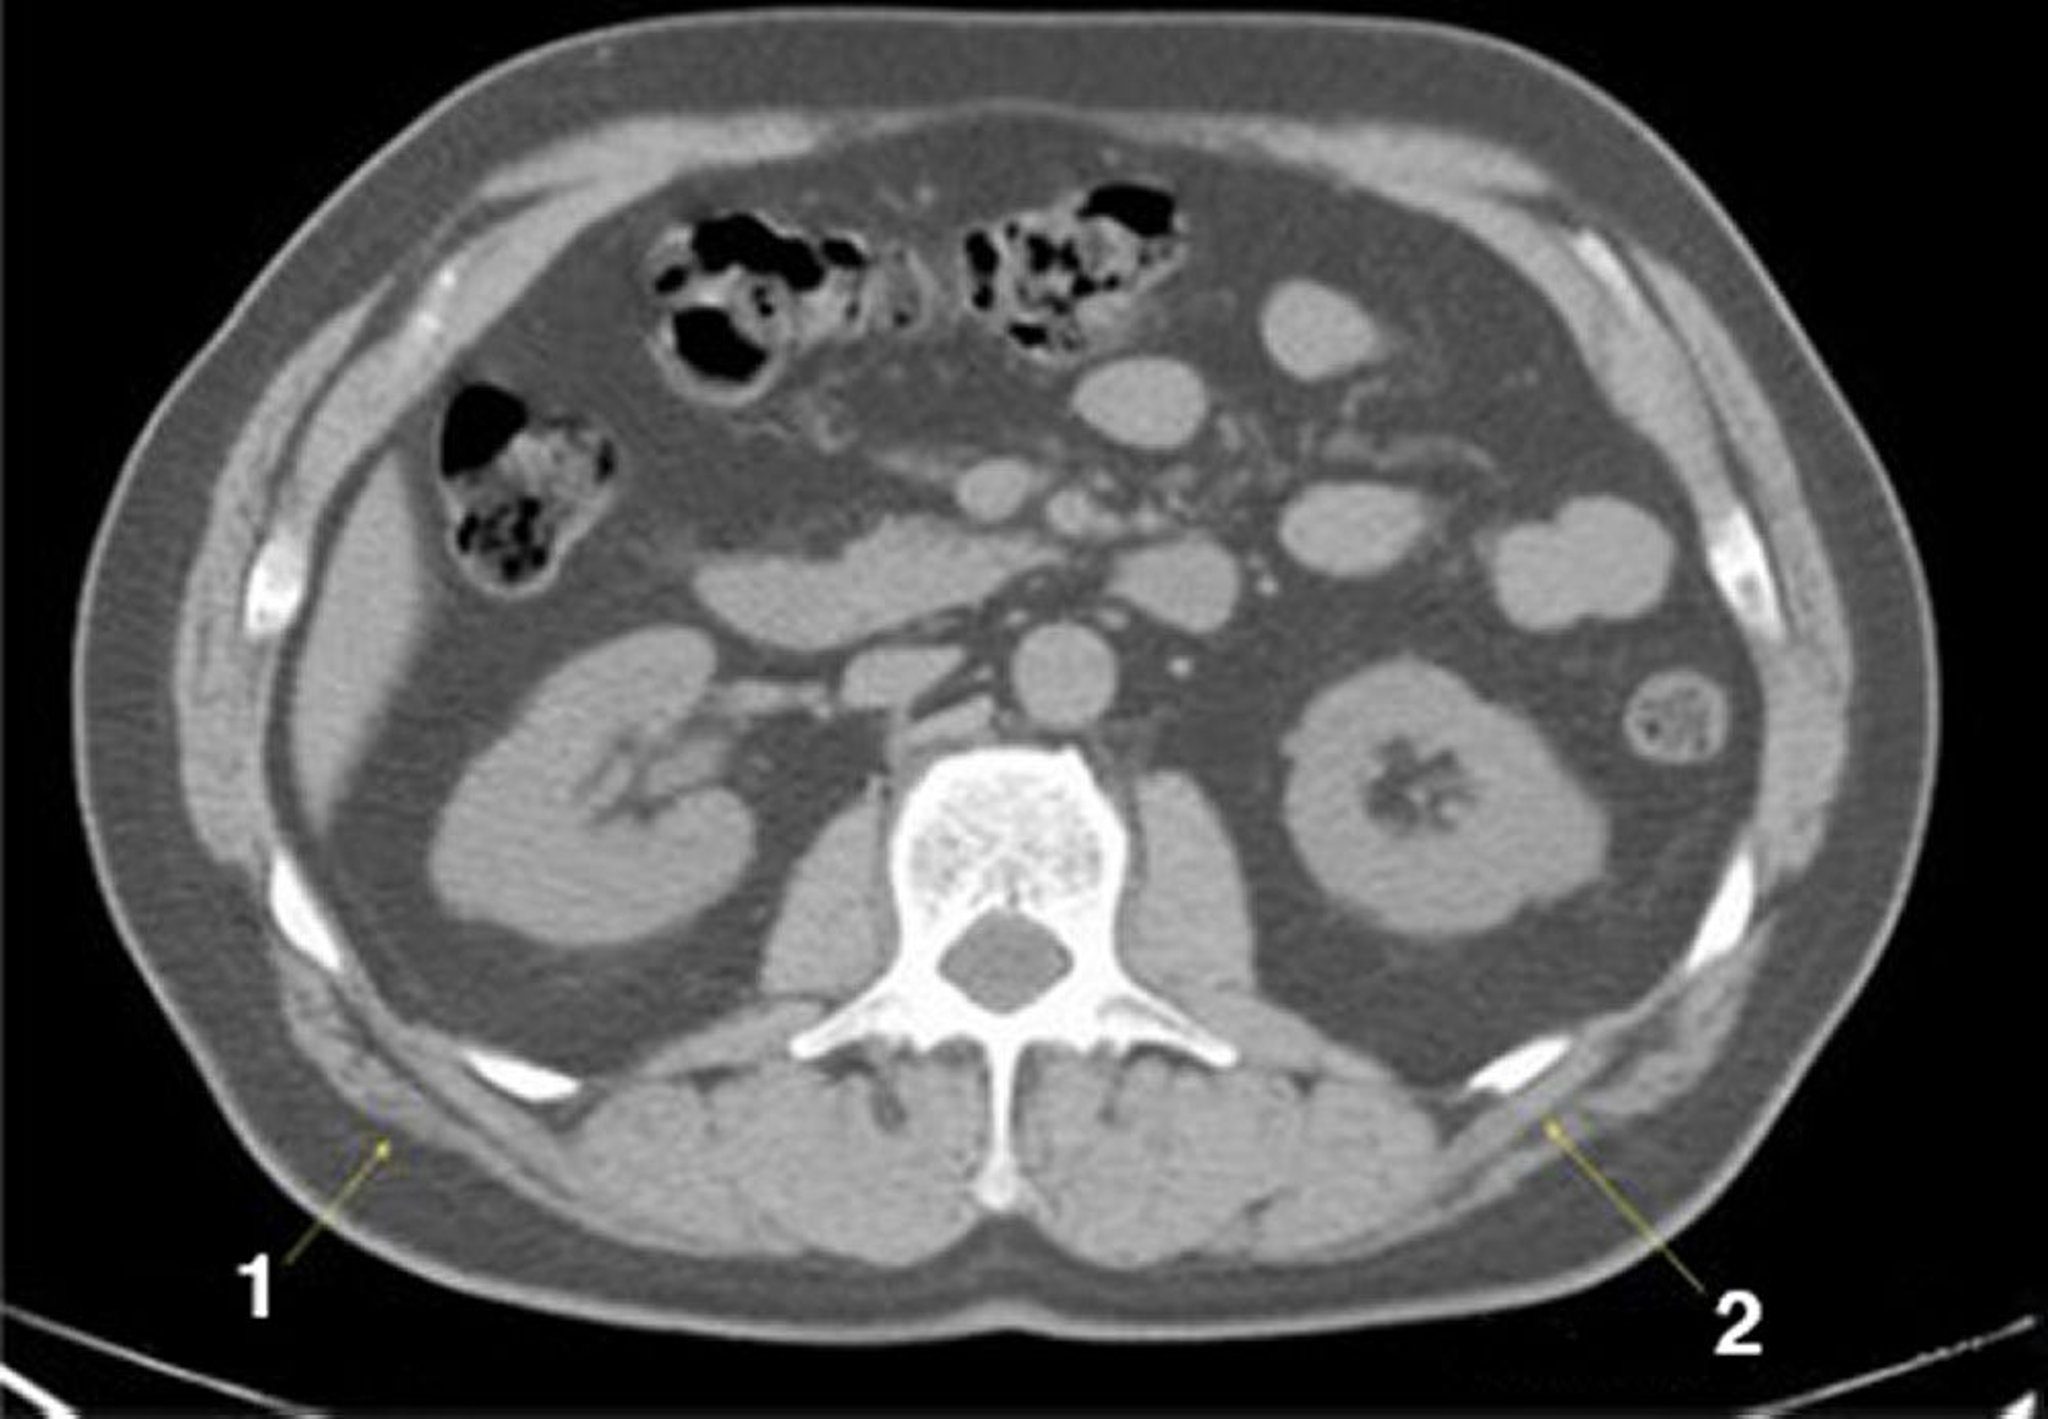

Phim chụp CT vùng bụng và vùng chậu không thuốc cản quang cho thấy giải phẫu bình thường (lát cắt 15)

1 = cơ lưng rộng; 2 = cơ răng sau.